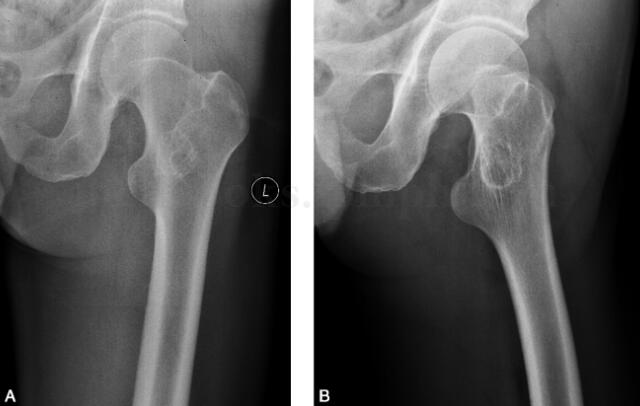

男,53岁,左髋部不适感1年余(图1~3)。

图1 DR:左股骨粗隆间见低密度区,周围可见硬化环